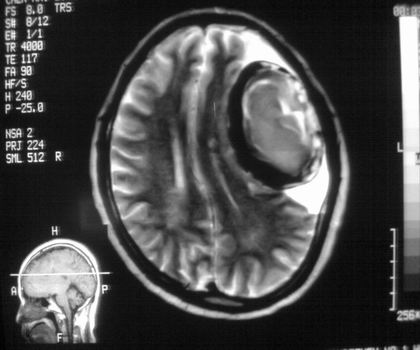

以下是引用影像孺子牛在2008-4-29 21:20:00的发言:[br]首先病变定位在脑外,根据ct密度及mri信号特征考虑慢性硬膜下血肿不连续环形钙化。

以下是引用周战梅在2008-4-29 23:12:00的发言:[br]脑外病变,蛛网膜下腔增宽,囊壁点状、环形钙化,增强扫描呈不均匀环状强化,考虑为囊性脑膜瘤可能性大,慢性脓肿、血肿机化、胆脂瘤不能除外。